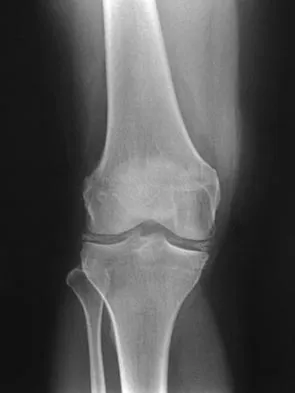

A 40-year-old woman reports the atraumatic onset of severe knee pain and swelling after undergoing an uncomplicated elective cholecystectomy 1 week ago. She denies any history of diabetes mellitus or HIV but has had occasional episodes of mild knee pain and swelling that have always responded to nonsteroidal anti-inflammatory drugs. Radiographs are shown in Figures 5a and 5b. A knee aspiration yields a WBC count of 35,000/mm3. The aspirate should also yield which of the following findings?

Explanation

The radiographs reveal chondrocalcinosis of the menisci. This is caused by calcium pyrophosphate crystals, which are weakly positive birefringent rhomboid-shaped crystals. Frequently, this condition is asymptomatic; however, routine abdominal surgery may cause precipitation of these crystals and pain. Gout, which is caused by strongly negative birefringent needle-shaped sodium urate crystals, is not associated with chondrocalcinosis and is rare in younger women. Gross blood is uncommon without trauma. Infection is not likely in a healthy patient who underwent uncomplicated surgery. Fisseler-Eckhoff A, Muller KM: Arthroscopy and chondrocalcinosis. Arthroscopy 1992;8:98-104.